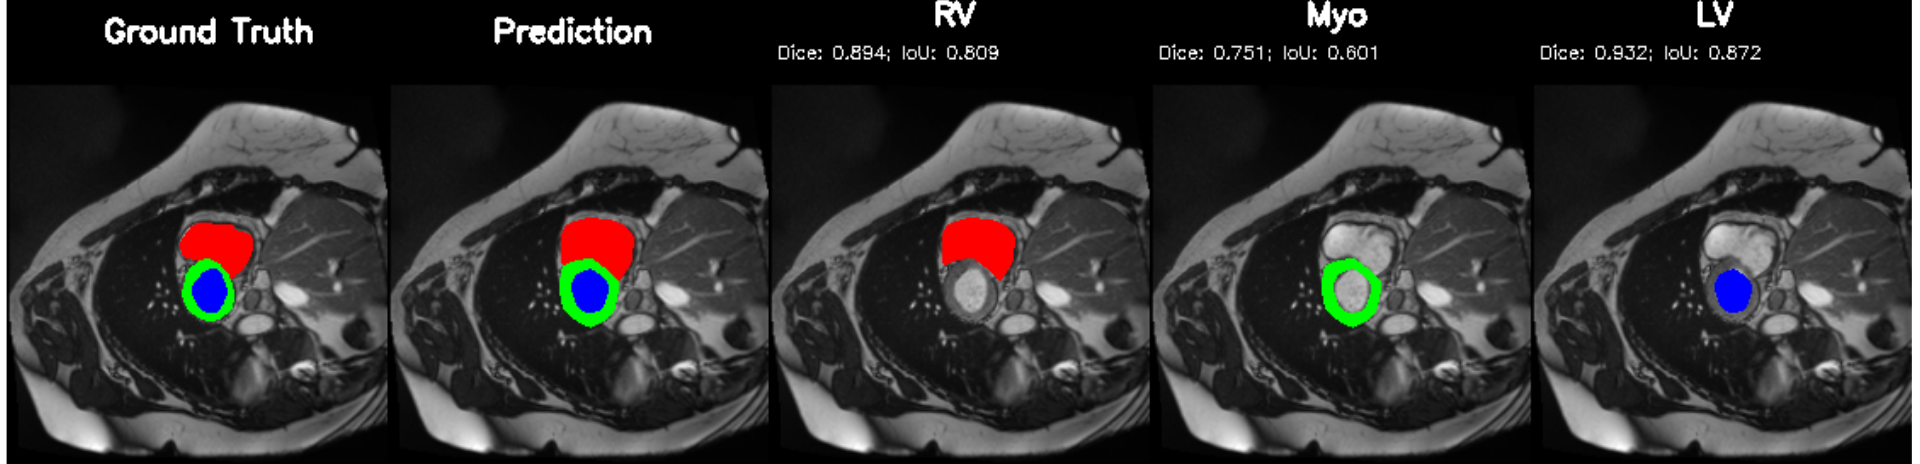

Figure 6 presents five representative subjects from the ACDC cohort: Dilated Cardiomyopathy (DCM), Myocardial Infarction (MINF), Hypertrophic Cardiomyopathy (HCM), Normal controls (NOR) and Right-Ventricular Abnormality (RVA). Consistent with the quantitative Dice distributions in Table 3, left ventricular (LV) cavities are cleanly isolated across all groups, while right-ventricular boundaries remain stable even in crescent geometries. In DCM, severe dilation is captured without cavity collapse; in HCM, myocardial thickening is preserved; and in MINF cases with infarct-associated thinning, the myocardium remains continuous rather than broken into sparse segments. Normal subjects exhibit the smoothest ring shaped myocardium, matching upper-bound segmentation behavior. To evaluate contraction dynamics rather than static masks alone, Figure 7 compares End-Diastole (ED) and End-Systole (ES) frames for the same pathologies. The model tracks temporal deformation faithfully, cavity size reduction, myocardial thickening and volumetric change remain physiologically coherent across systole. This visual behavior aligns with the clinical error analysis in Table 5, where ejection-fraction (EF) and volume-derived indices fall within accepted diagnostic tolerance ranges without handcrafted post-processing. The strong coupling between segmentation integrity and diagnostic separation also correlates with the elevated disease classification accuracy reported in Table 4. Despite strong performance, qualitative inspection highlights a recurring limitation: myocardium remains the most challenging region. Mild indistinctness can occur at basal planes or within highly trabeculated right ventricular zones, reflecting the lower Myo Dice relative to LV and RV. These patterns suggest future work may benefit from boundary-aware refinement modules, shape priors or contour-focused supervision to reduce subtle wall blurring. The qualitative evidence supports the quantitative findings, PULSE generalizes across structural variations, maintains temporal physiologic consistency between cardiac phases, and delivers masks sufficiently accurate to support automatic functional index computation and cardiomyopathy recognition.

5.2 M&Ms Cine-MRI Generalization

Figure 8 illustrates segmentation outputs on the M&Ms (Multi-Centre, Multi-Vendor) cine-MRI dataset, which exhibits both contrast variation and vendor–specific acquisition differences compared to ACDC. The model retains consistent ventricular geometry, recovering LV and Myocardium structure without retraining, mirroring the zero-shot Dice performance of 74.8% (Table 11). Boundary thickness remains physiologically accurate, with only minor degradation in the right ventricle, an expected behaviour under cross-domain shifts and also reflected quantitatively in the ablation-driven robustness improvements from normalization and loss design. These results demonstrate that PULSE does not overfit to a single scanner distribution but instead transfers cardiac structure priors across unseen clinical environments.